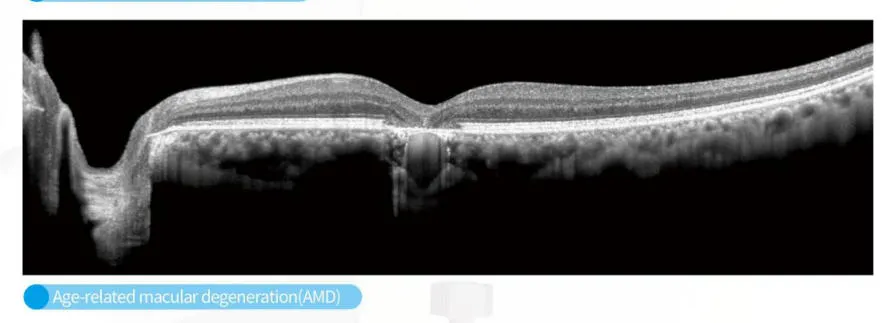

OCT Imaging Analysis

OCT Structural Scan

The C800 incorporates automatic eye-tracking, SLO scanning, and multi-mode tomographic imaging, ensuring stable visualization even for patients with difficulty maintaining fixation. Advanced choroidal thickness measurement and macular mapping support precise monitoring for myopia control, diabetic retinopathy, glaucoma, and age-related macular degeneration.

It is ideal for monitoring and detecting myopia, diabetic retinopathy, glaucoma, and age-related macular degeneration through advanced choroidal and macular mapping.